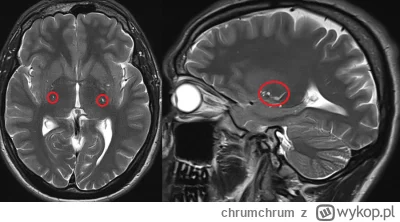

Czy jest ktoś w stanie mi wytlumaczyc dlaczego nagle mogla mi sie zacząć trzęść szyja i kark? Za każdym razem jak napne kark przykładowo przy ruszaniu głową albo gdy np. robie planka albo probuje sie na drążku podciągnąć, czy zwyczajnie zmienić pozycje na krześle to czuje jak mi zaczyna drżeć cały kark jak galareta i za tym idzie głowa. Nigdy wcześniej tak nie miałem, a trwa to już z 2 miesiące i